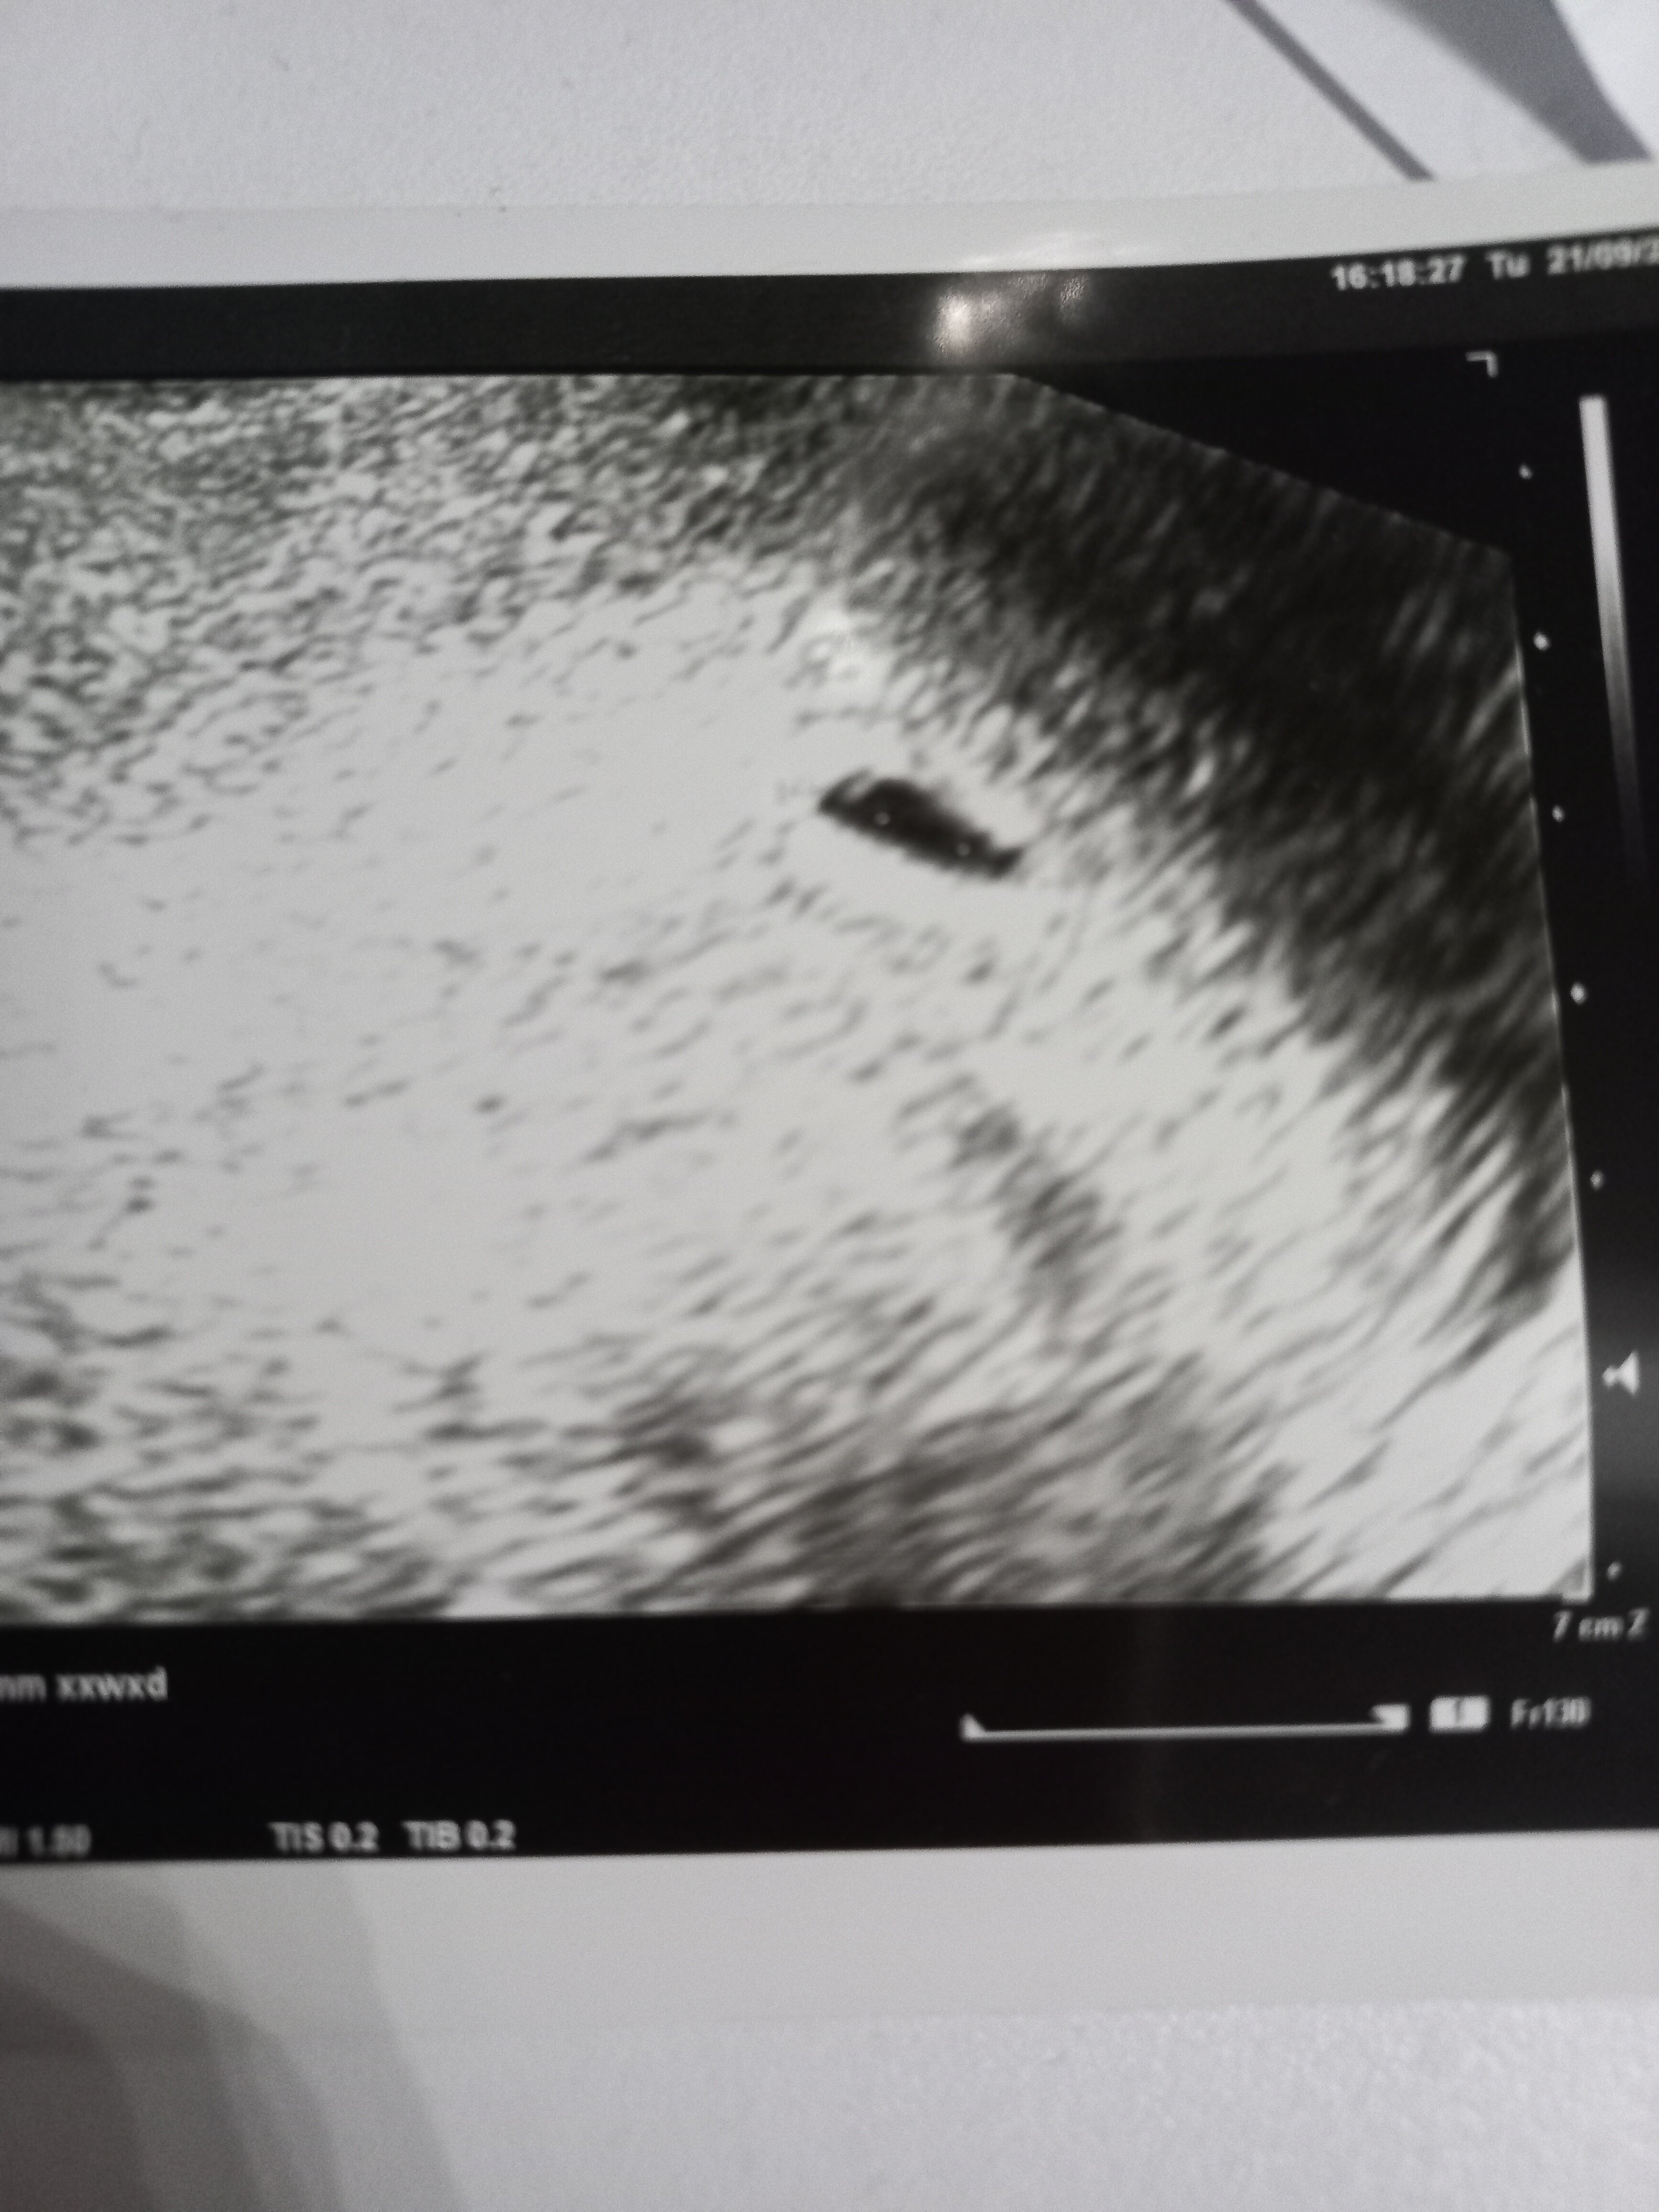

Pierwsze usg. Pęcherzyk ciążowy

Wczoraj 21.09 byłam u ginekologa (według miesiączki 4tc6d) Powiedzial mi że jest pęcherzyk ciążowy 6.7 mm narazie bez zarodka.

• 20210922_193115.jpg

20210922_193115.jpg

1,5 MB · Wyświetleń: 383